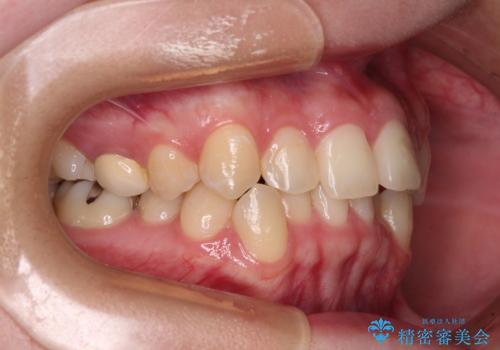

前歯のクロスバイト ギラギラのワイヤー装置で矯正治療

- 前歯のクロスバイトを改善したいとのことで来院された患者様です。

クロスバイトが改善する際は、前歯しか接触しないため、痛みがあったり食事が取りにくかったりと、不便な時期がありますが、1年強の短期間で無事に治療を終えることができました。